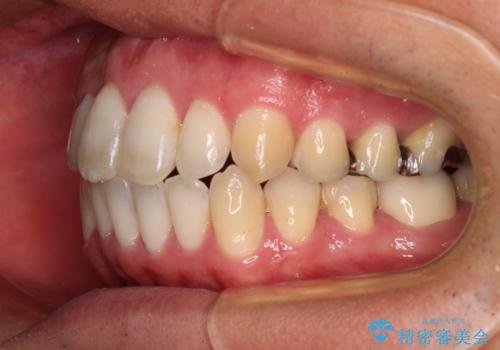

上顎歯列全体を後方に移動させたため、口元の突出感も改善され、装置を外してからは口が閉じやすくなりました。

また、上下犬歯が接触するようになったため、奥歯にストレスのかからない歯ぎしりができるようになり、顎の疲れも改善されました。